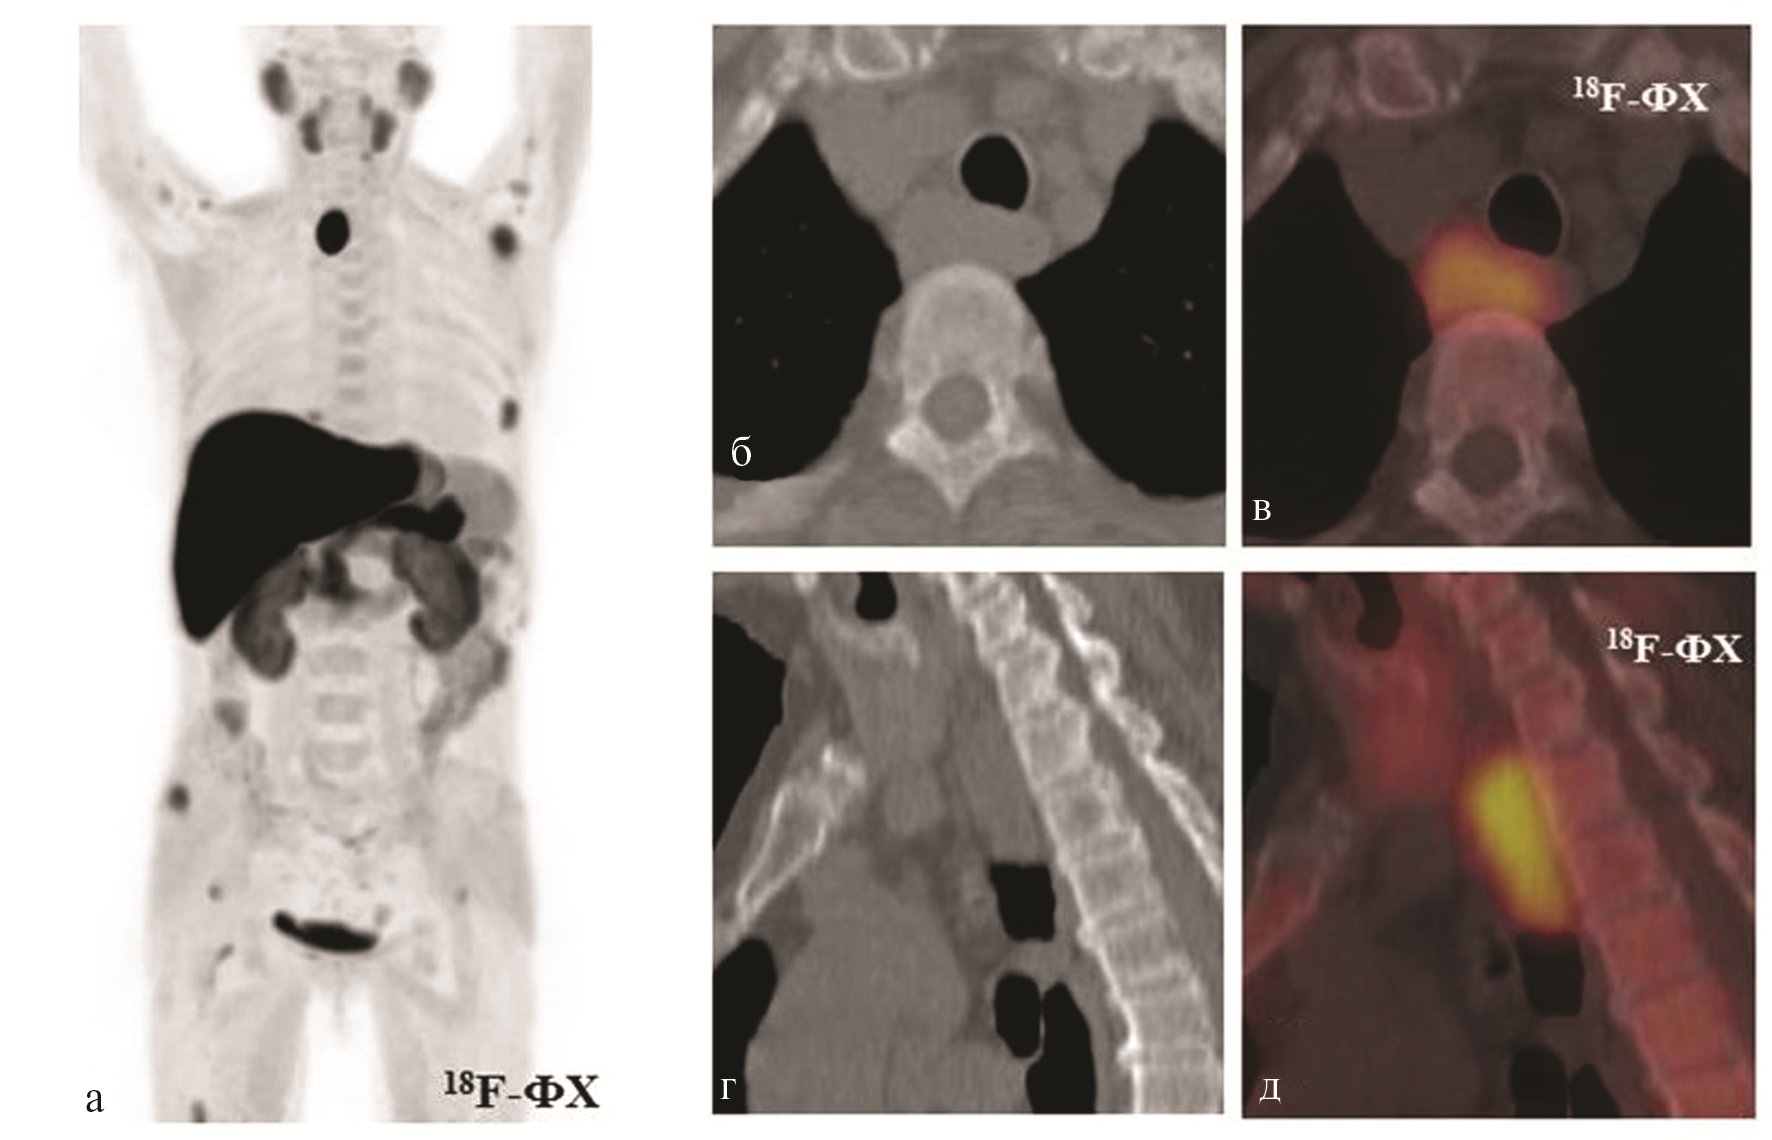

На фоне форсированного диуреза и приема цин акальцета (90 мг/сут) сохранялась выраженная гиперкальциемия: уровень общего кальция 3,09 ммоль/л. Учитывая тяжелое течение ПГПТ и наличие крупной опухоли ОЩЖ, у пациентки была заподозрена карцинома ОЩЖ. С целью оценки распространенности процесса и исключения метастатического поражения, а также для уточнения размера и локализации загрудинно расположенной опухоли, больная была направлена в ФГБУ «НМИЦ онкологии им. Н.Н. Блохина» для проведения ПЭТ/КТ. В качестве диагностического РФП был выбран 18F-ФХ. При ПЭТ/КТ определялись очаги патологического накопления в объемном образовании ОЩЖ на уровне ThI-ThIII превертебрально (справа от пищевода и трахеи) размером 26×18 мм, протяженностью до 43 мм, с максимальным накоплением SUV 8,60; пищевод и трахея на уровне образования смещены влево (рис. 4, на цв. вклейке). Очагового повышения накопления РФП в зонах типичного расположения ОЩЖ выявлено не было. При КТ в костях определяются множественные разнокалиберные очаги деструкции со структурными изменениями, характерными для «бурых опухолей». Накопление 18F-ФХ в очагах деструкции варьировало от макс. SUV 2,80 до 6,88. Повышенное накопление РФП в некоторых очагах костной деструкции отсутствовало. Для демонстрации мы выбрали два очага – в акромиальном отростке левой лопатки и средней трети левой бедренной кости (рис. 5, на цв. вклейке).

Рис. 4. Результаты лучевой диагностики пациентки А. (стрелками указана дистопированная в верхнее средостение ОЩЖ, ПЭТ/КТ с 18F-ФХ).

а — ПЭТ с 18F-ФХ (проекция максимальной интенсивности); б, в — КТ и совмещенные ПЭТ/КТ аксиальный срез верхнего средостения — очаг патологического накопления в ОЩЖ; г, д — КТ и совмещенные ПЭТ/КТ, этот же очаг — фронтальный срез.

Рис. 5. Результаты лучевой диагностики пациентки А. (стрелками указаны патологические очаги в костях, ПЭТ/КТ с 18F-ФХ).

а, б — очаг литической деструкции в седалищной кости слева с патологическим накоплением РФП (КТ и совмещенный ПЭТ/КТ, аксиальные срезы); в, г — очаг литической деструкции в головке левой плечевой кости с патологическим накоплением РФП (КТ и совмещенный ПЭТ/КТ, аксиальные срезы); д, е — очаг литической деструкции в крыле правой подвздошной кости без патологического накопления РФП (КТ и совмещенный ПЭТ/КТ, аксиальные срезы).